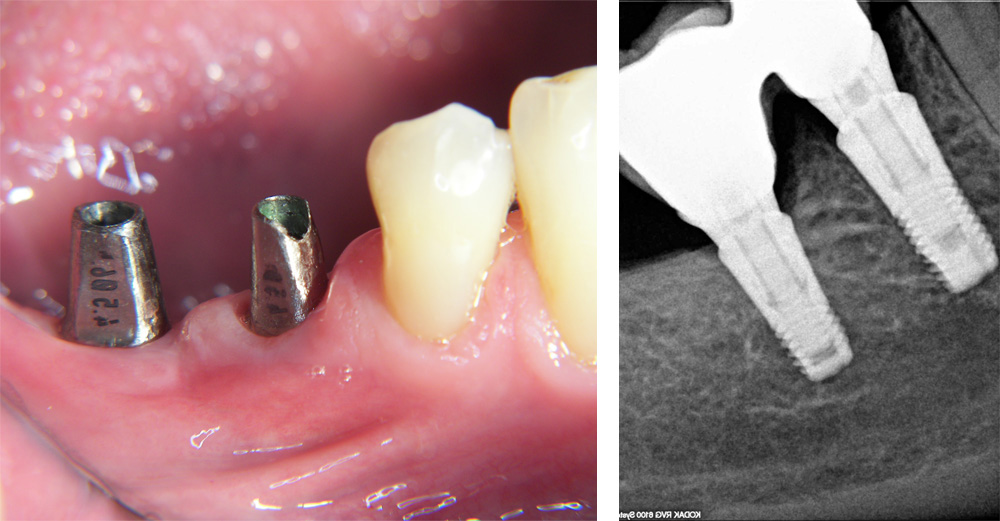

Titanske nadogradnje i rendgenski prikaz postavljenih implantata